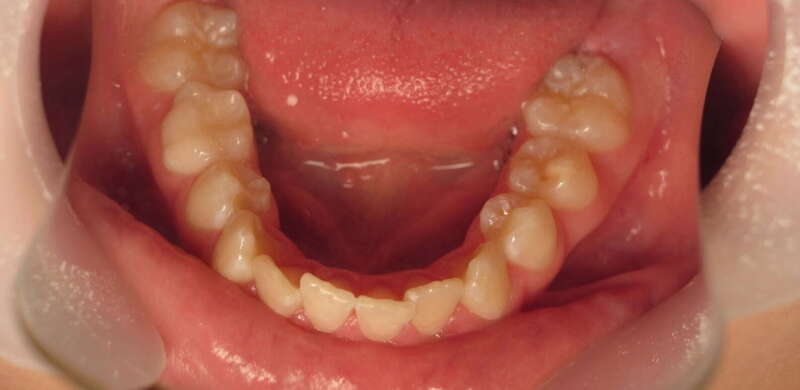

Cas n°1 traité par aligneurs (interception) - enfant

Ce cas d’interception chez un enfant de 8 ans démontre l'efficacité des aligneurs pour corriger des troubles fonctionnels précoces. Le diagnostic présentait des inversions d'articulé provoquant une déviation de la mandibule vers la gauche et un décalage des milieux.

Grâce à une coopération exemplaire et un traitement totalement indolore, l'expansion de l'arcade a permis de recentrer la mâchoire. Cette intervention a littéralement remis la croissance sur les rails, neutralisant le risque d'asymétrie faciale squelettique.

• Correction fonctionnelle : Recentrage immédiat de la mandibule et des milieux inter-incisifs.

• Prévention : Création d'un environnement favorable pour les dents définitives à venir.

• Bien-être : Approche douce respectant le confort de l'enfant.

C'est une étape fondamentale qui simplifie l'avenir orthodontique du patient tout en garantissant un développement facial harmonieux.